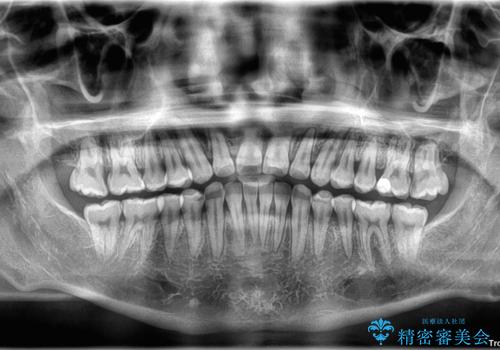

**前歯のデコボコ(叢生)**が整い、歯列全体が美しく改善

シザーズバイトの奥歯も正常なかみ合わせに改善

捻転歯も回転が修正され、全体的に清掃性・咀嚼効率が向上